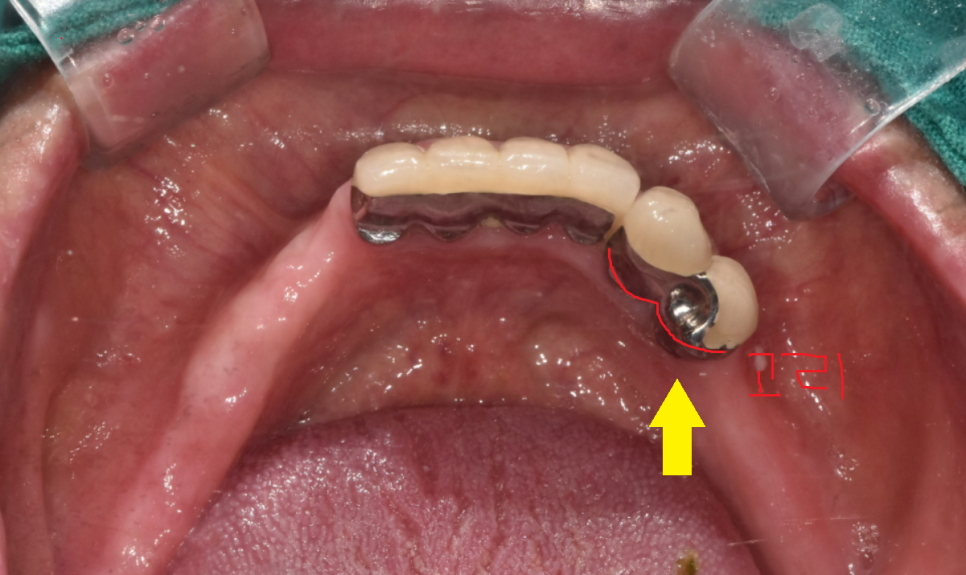

임플란트로 교체 하고나면

단순히 수술로 끝나서는 안됩니다.

일반적으로는 임플란트는 머리 완성 후

교합을 맞춰드리고 치료는 종결이지만

틀니 사용중 치아 부러짐으로

임플란트 치료를 하게되면

고리를 걸어서 사용하기 때문에

틀니가 잘 걸리게

기존 틀니를 수리까지 해주어야 완성됩니다.

240125

틀니 수리까지 하여

편안하게 쓰실 수 있도록 치료를 끝내드렸습니다.